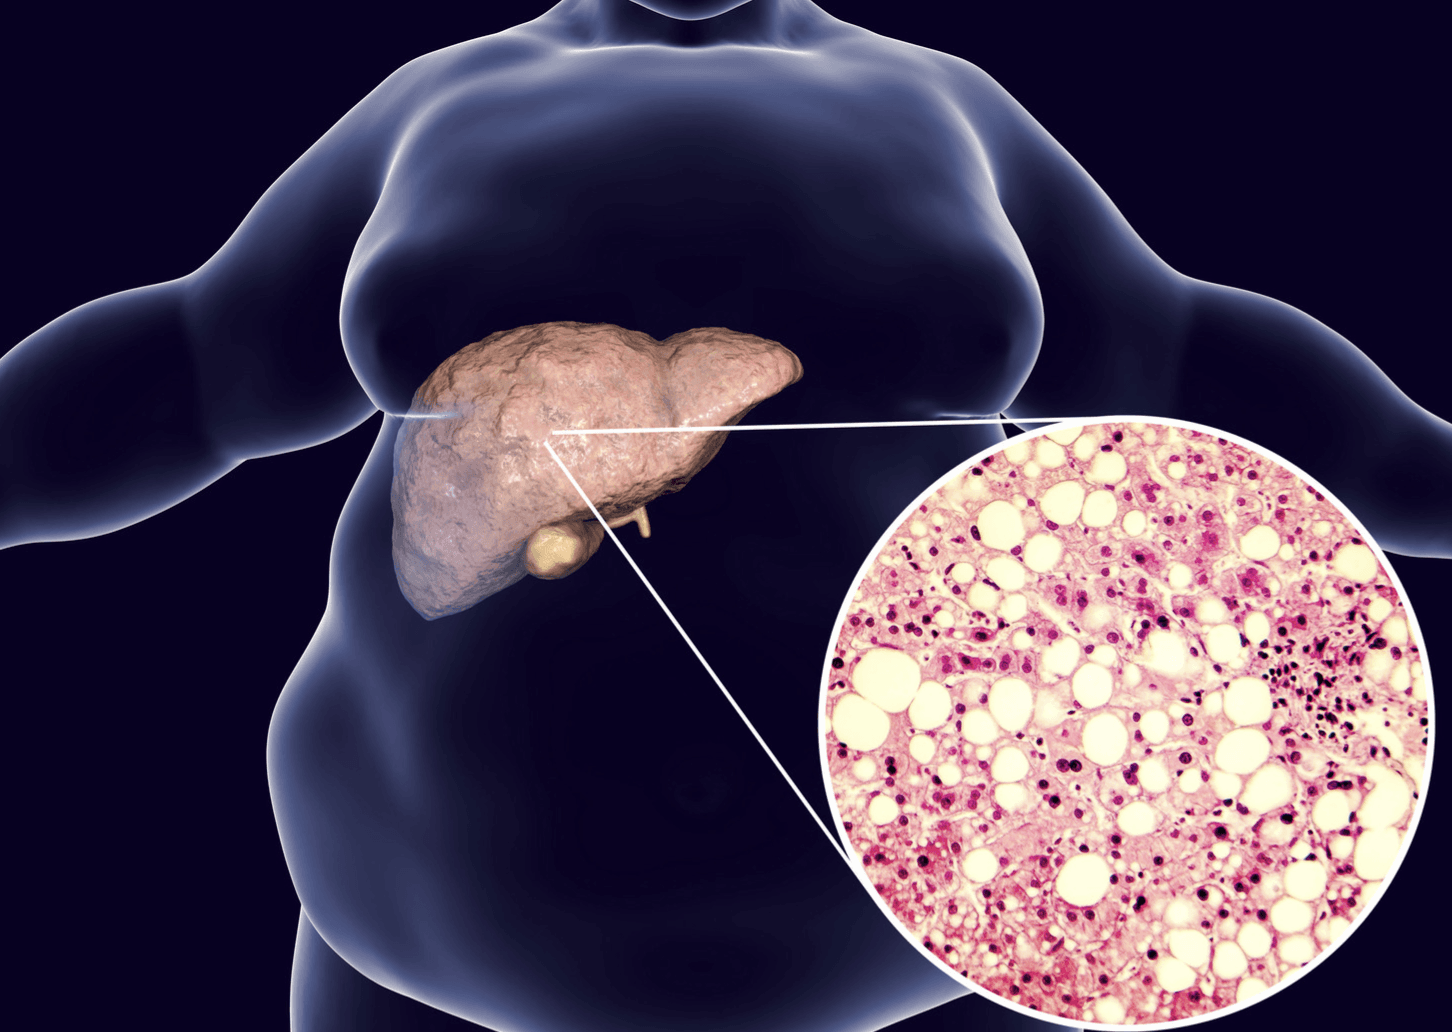

Could a silent condition be putting your liver at risk? Fatty liver disease, a condition characterized by the excessive buildup of fat in the liver, is becoming an increasingly significant health concern worldwide. It affects a substantial portion of the global adult population, with estimates ranging from 30% to 32%. This makes it a leading cause of liver disease globally, and its prevalence is unfortunately on the rise. While a small amount of fat in the liver is normal, when this fat accumulation exceeds 5-10% of the liver's weight, it signifies the presence of fatty liver disease. Often, this condition progresses without noticeable symptoms in its early stages, leading many to be unaware of the potential danger. Understanding what fatty liver disease is, its causes, and how to manage it is crucial for safeguarding your long-term health. There are two primary types of this condition: alcoholic fatty liver disease, which is linked to excessive alcohol consumption, and nonalcoholic fatty liver disease, which occurs in individuals who do not drink heavily.

The liver, a vital organ responsible for numerous bodily functions, including digestion and detoxification, normally contains a small amount of fat. However, when the fat content surpasses 5-10% of the liver's total weight, it is classified as fatty liver disease, also known as steatosis. This seemingly simple accumulation can have significant implications for liver health over time.

Nonalcoholic fatty liver disease (NAFLD), now often referred to as metabolic dysfunction-associated steatotic liver disease (MASLD), describes a condition where there is a buildup of fat in the liver that is not primarily caused by heavy alcohol use. Within NAFLD, there are two main categories: nonalcoholic fatty liver (NAFL), also known as metabolic dysfunction-associated steatotic liver (MASL), where fat is present in the liver with little or no inflammation or liver damage, and nonalcoholic steatohepatitis (NASH), now called metabolic dysfunction-associated steatohepatitis (MASH), which involves fat in the liver along with inflammation and potential liver damage. NASH/MASH is considered a more serious form of NAFLD/MASLD because the inflammation and damage can lead to complications like fibrosis (scarring) and cirrhosis.